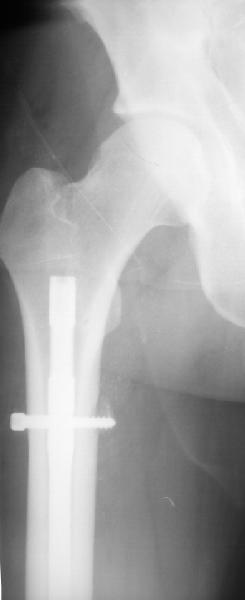

Если как на приложенной картинке - мало места?